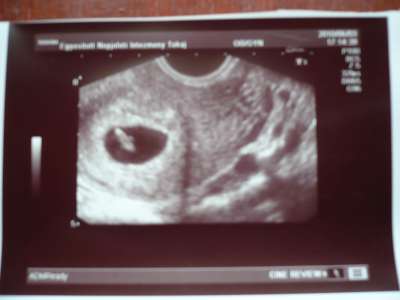

Ma voltam UH-n és jó híreklet kaptam!

Jó helyen van a pici,hallottam a szívverését 8mm-es és 7 hetesnek felel meg.

2 hét múlva kellesz újra mennem!Most nagyon boldog vagyok!

Rodina:8mm-nek mérték!Azt mondta,hogy 7 hetesnek felel meg!Szerinted nem kicsi?

A mi babónk 7 hetesen volt 8,3 mm-es. Úgyhogy nem kell aggódni, minden rendben van, nem kicsi!

Nem, még nem érzek magzatmozgást. Van, hogy néha érzek olyan furi dolgokat, de még egyik sem az volt, hogy biztosan tudtam volna, hogy a pici mozgott. Még 2-3 hét és biztosan érezni fogom!